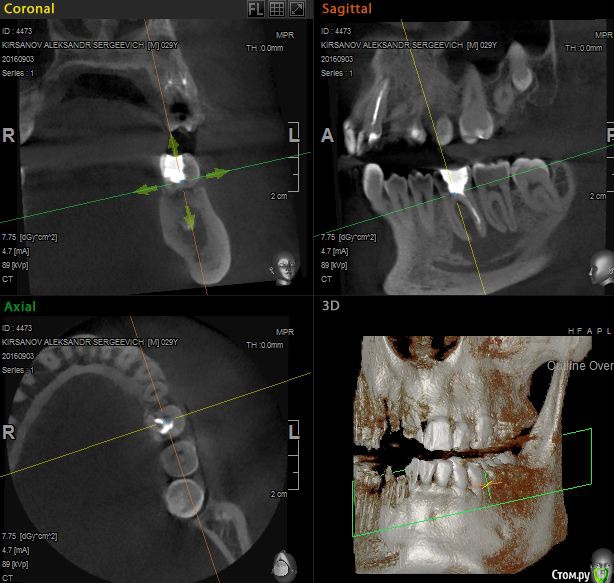

St. Опубликовано 12 ноября, 2016 Поделиться Опубликовано 12 ноября, 2016 Выложу скрины приложенного КТ. Так ответов будет больше. Есть пропущенный канал в 6 зубе. И нужно проверить на жизнеспособность соседний 7. Я бы рекомендовала попробвать перелечить и понаблюдать. Но Вы должны для себя понимать что перелечивание каналов очень сложная, дорогая и непрогнозируемая процедура. Хотя вероятность успеха достаточно высока. Если хотите гарантий - тогда удаление и имплант как восстановится кость. Еще хорошо бы знать как давно лечили каналы в этом зубе, как он вел себя после лечения, беспокоит ли сейчас? 2 Ссылка на комментарий

DmitrySH Опубликовано 12 ноября, 2016 Поделиться Опубликовано 12 ноября, 2016 Все верно написала.Отвлекусь от "кисты" на ОПТГ, что с 11,21? артефакты? Ссылка на комментарий

St. Опубликовано 12 ноября, 2016 Поделиться Опубликовано 12 ноября, 2016 11, 21 по кт без особенностей. Так что артефакты скорее всего. В 23( левый клык) есть тоже воспаление на корне. Нужно планово перелечиавать. Ссылка на комментарий